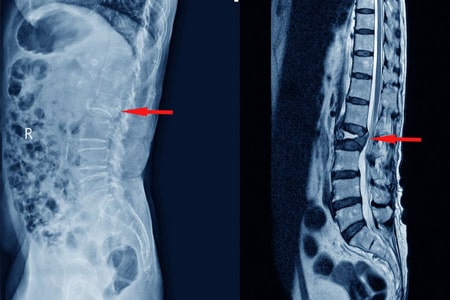

Lumbalgia

Existe una importante brecha entre las recomendaciones basadas en la evidencia y la práctica clínica en el dolor lumbar inespecífico, tanto agudo como persistente, con un uso limitado de intervenciones de alto valor y un uso excesivo de las de bajo valor como: pruebas de imagen, reposo, medicamentos como opioides o gabapentinoides, o cirugía.En este número del boletín se revisa la evidencia disponible sobre la eficacia de diferentes tipos de intervenciones en el manejo de la lumbalgia inespecífica, tanto aguda como persistente. INFAC, CEVIME, 26 de noviembre de 2024